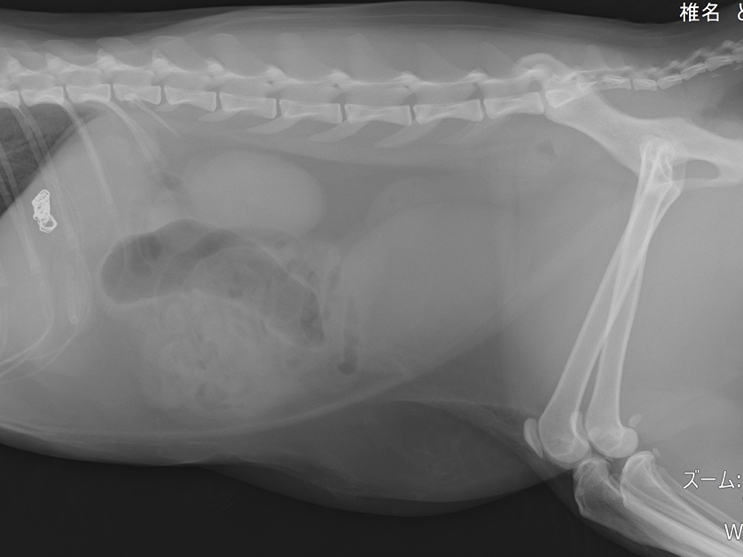

術後のレントゲン画像